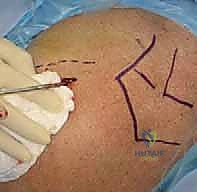

تتطلب هذه العملية دقة متناهية وفهماً عميقاً للتشريح ثلاثي الأبعاد للكتف، وهو ما يبرع فيه البروفيسور هطيف. إليكم كيف تتم العملية داخل غرف العمليات المجهزة بأحدث التقنيات في صنعاء:

1. التخدير والتجهيز

يتم إخضاع المريض للتخدير العام أو التخدير الموضعي (إحصار العصب). يُوضع المريض في وضعية "كرسي الشاطئ" (Beach Chair) أو الاستلقاء على الظهر، مما يتيح للجراح وصولاً كاملاً للكتف وحرية في استخدام جهاز الأشعة.

3. الرد المغلق للكسر (Closed Reduction)

بمهارة يدوية فائقة، يقوم الدكتور هطيف بإعادة الشظايا العظمية إلى مكانها التشريحي الصحيح عن طريق سحب الذراع وتدويرها بآليات محددة، كل ذلك تحت مراقبة الأشعة.

صور إضافية من داخل غرفة العمليات توضح دقة الإجراء: